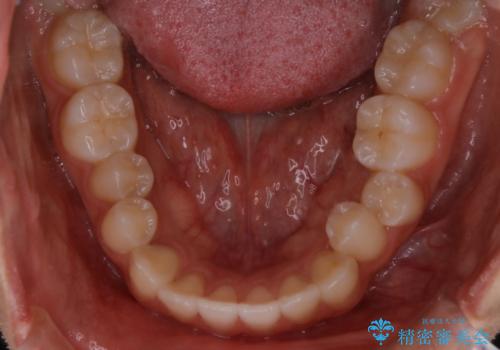

- 受け口の改善と前歯のガタつきの治療を主訴にご来院されました。

こちらの患者様の場合、上の前歯のガタつきが原因で口を閉じる際に上下の前歯の先端同士が先に当たってしまい、そこからさらに深く噛み込もうとすると下顎が前にずれていってしまうという、機能性の反対咬合であることが検査の結果わかりました。

そのため、まずは上顎の前歯のガタつきを改善していき、前歯が先に当たってしまうという症状を改善し噛み込む位置を後方の本来の位置に誘導する方法をとりました。